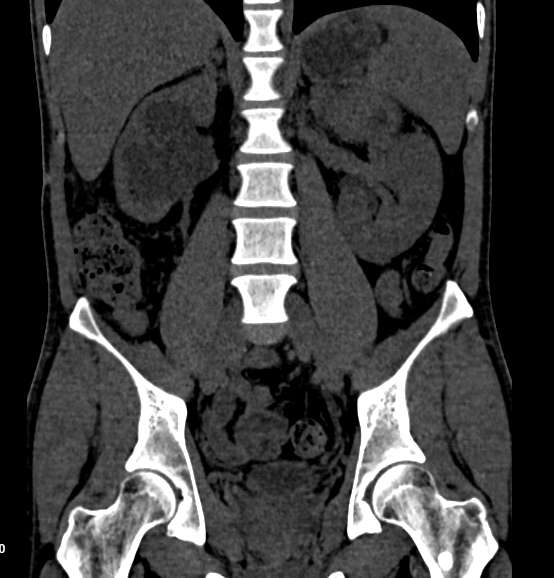

Right Kidney:

- Size and Shape: Measures 11.4 x 5.1 cm; normal in size and shape.

- Condition: Markedly dilated right renal pelvicalyceal system with abrupt narrowing at the pelvi-ureteric junction. Cortical atrophy noted.

- Calculi: Multiple varying-sized calculi in the lower calyx; largest measures 15 x 9 mm (HU value 900-1050).

- Perinephric Fat: Mild stranding noted.

Left Kidney:

- Size and Shape: Measures 11.7 x 4.7 cm; normal in size and shape.

- Condition: No calculi, hydronephrosis, or contour deforming lesion.

- Perinephric Fat Planes: Clear.

Impression:

- Right Pelvi-Ureteric Junction Obstruction: Moderate hydronephrosis and cortical thinning.

- Multiple Right Renal Calculi